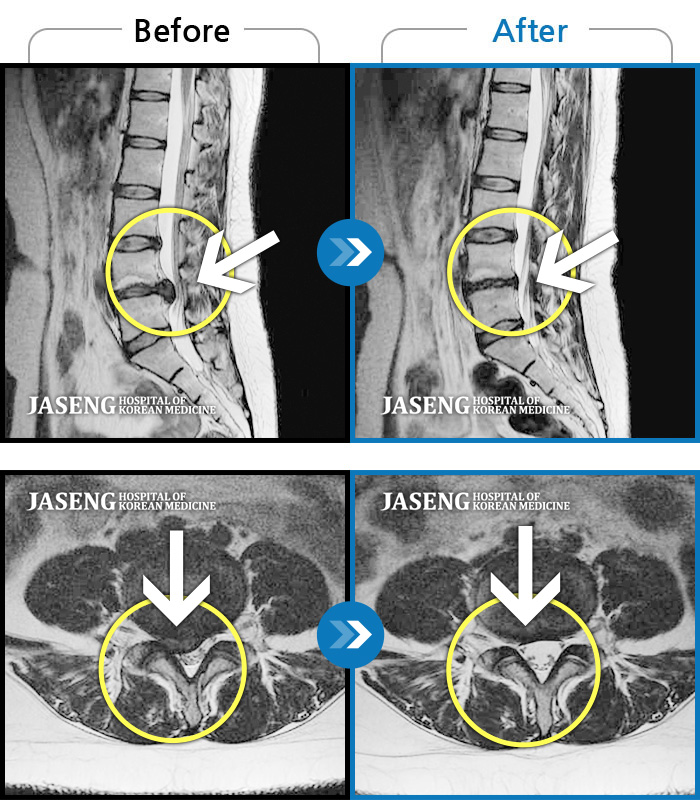

허리디스크

잠실 · 한상욱 원장

우측 엉치부터 우측 다리부터 발끝까지 저리고 아프다. 감각까지 먹먹하다.

촬영시기

2022.04.15 ~ 2022.10.22

2022.12.02